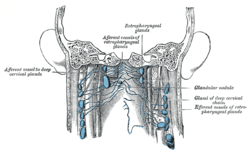

Lymphatics of pharynx.